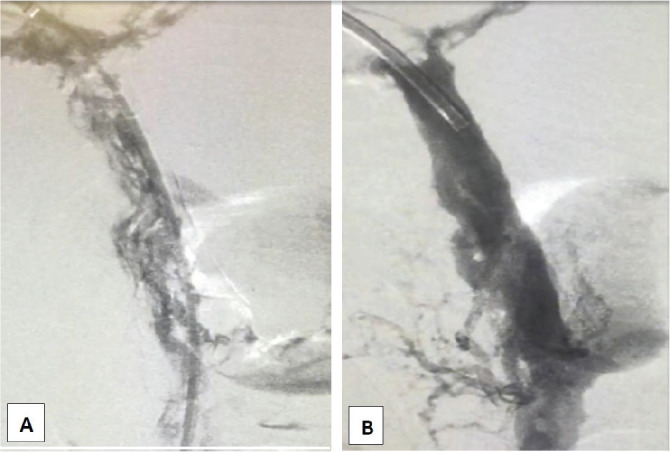

急性肠系膜缺血是一组疾病,它导致小肠血流突然中断,导致小肠坏死。其首发症状模糊,多数病例无特异性,因此诊断怀疑对于建立正确诊断和及时治疗至关重要。这是一个复杂而困难的事件,需要多学科的方法,涉及不同的专业,如胃肠道和血管外科医生,介入放射科医生,以及来自急性护理小组的专业知识。最基本的方面是基于腹部计算机血管断层扫描的早期诊断和立即重建受影响区域的血液供应。在本报告中,我们介绍了一例肠系膜静脉血栓患者,由于抗凝入路后临床反应不佳,需要机械通气,经皮血管内治疗(门静脉-肠系膜机械取栓,静脉溶栓输注)。

Acute mesenteric ischemia represents a group of diseases, which lead to an abrupt interruption of blood flow to the small intestine resulting in intestinal necrosis. Its first symptoms are vague and in the majority of cases nonspecific, so the diagnostic suspicion is of the utmost importance to establish the correct diagnostic and prompt treatment. It is a complex and difficult event, that needs a multidisciplinary approach involving different specialties such as gastrointestinal and vascular surgeons, interventional radiologists, and expertise from the acute care unit team. The fundamental aspect is the precocity of diagnostic based on abdominal computed angio-tomography and the immediate re-establishment of blood supply to the affected areas. In this report, we introduce a case of a patient with mesenteric venous thrombosis, who has beenundergone a percutaneous endovascular treatment (portal-mesenteric mechanical thrombectomy, besides an intravenous thrombolytic infusion), due to poor clinical response after anticoagulation approach that needed mechanical ventilation.